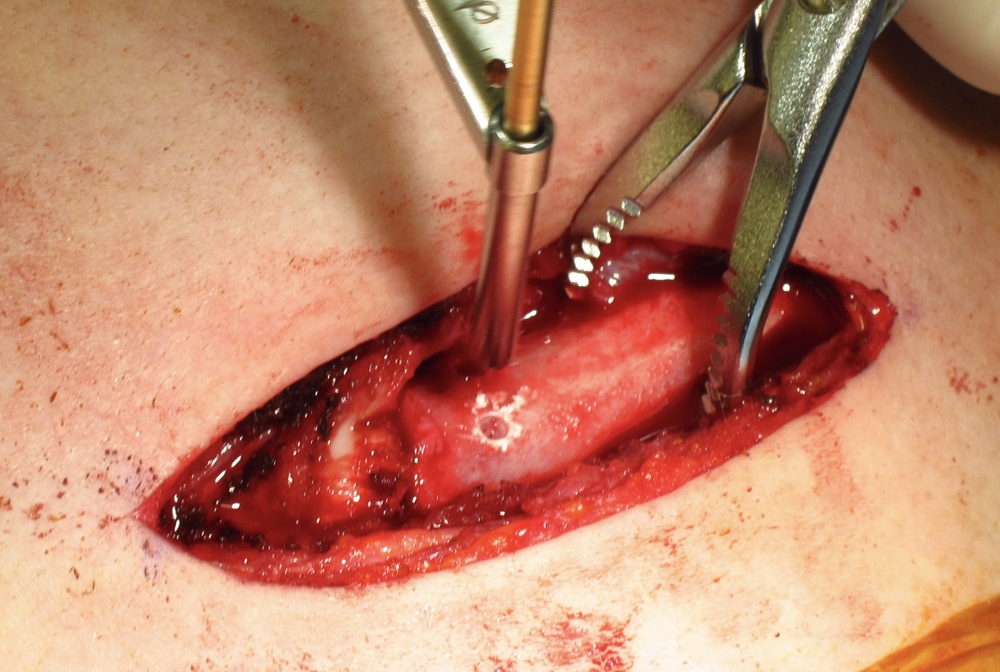

Open reduction of acute posterior sternoclavicular joint dislocation

Drill holes in manubrium and medial clavicle

Figure of 8 suture fixation